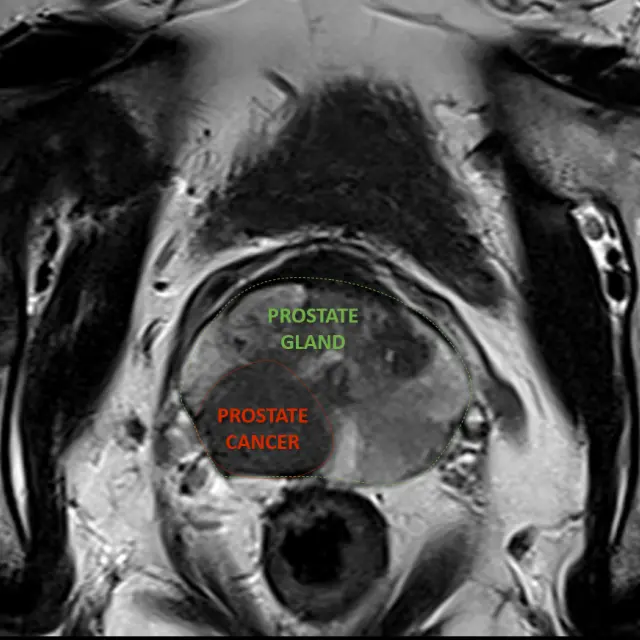

Canopy news Latest news and info from Canopy Healthcare September 17 2024 Discover Screening Options for Prostate Cancer Awareness Prostate cancer SPECT/CT As part of Prostate Cancer Awareness Month, explore available imaging options and better understand these important diagnostic processes. Learn more today. Read more September 18 2023 Unlocking the Advantages of Magnetic Resonance Imaging for Prostate Cancer MRI Prostate cancer Read more